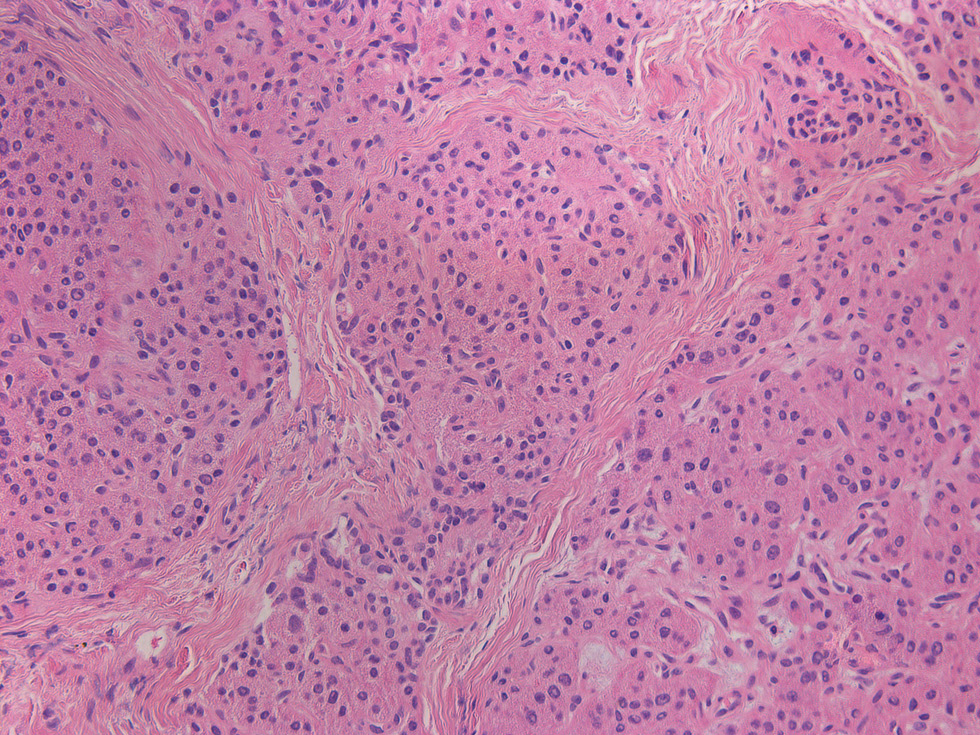

Несмотря на относительную эугликемию у части больных на фоне лечения октреотидом или диетотерапии, всем пациентам было проведено хирургическое вмешательство. Показания к оперативному лечению были обусловлены высоким риском развития гипогликемии на фоне пропуска приема пищи, тахифилаксией при применении октреотида, а также возможностью полного излечения после проведения резекции фокуса [23]. Большей части (25/31) детей выполнена резекция участка аденоматоза с проведением интраоперационной гистологической диагностики для оценки края иссечения (рис. 4). Проведение субтотальной панкреатэктомии пациентам с фокальной формой ВГИ было связано с отсутствием возможности проведения полной предоперационной диагностики, в частности ПЭТ/КТ с 18F-ДОФА на момент обследования.

Рис. 4. Гистологическое исследование ткани поджелудочной железы у пациента с фокальной формой ВГИ.

а – фокус гиперсекреции инсулина, метаплазия островков (окраска гематоксилином и эозином, ×20); б – выраженная экспрессия инсулина в фокусе при проведении иммунногистохимии; в – ткань поджелудочной железы вне фокуса гиперсекреции инсулина (окраска гематоксилином и эозином, ×200); г – низкая экспрессия инсулина вне фокуса при проведении иммунногистохимии.